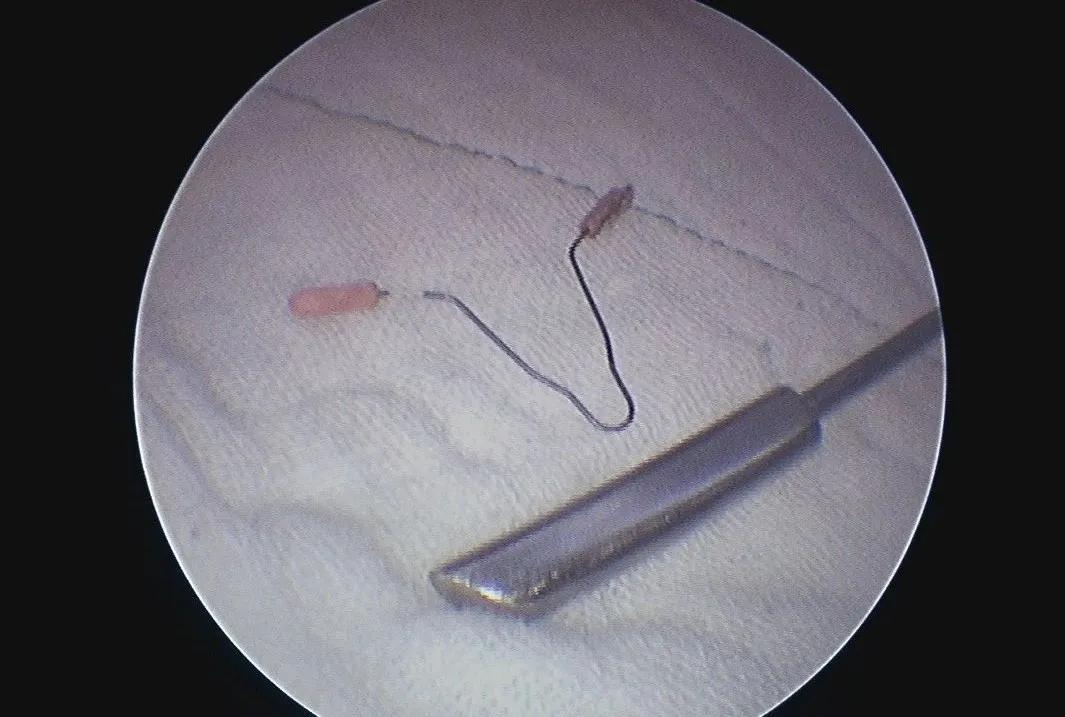

在手术室、麻醉科支持下手术开始,何晓北用钬激光一点点的将两枚结石击打成小碎块,随着结石的去除,节育环渐渐露出了真容,粉红色的两个端头丝毫不像能给患者带来剧烈腹痛的样子。何晓北用激光击打节育环的金属丝,靳永池带领的外一科团队紧盯着屏幕,做好了实施第二、三套方案的准备。随着几次亮光闪烁,节育环成功打断,接着从另一侧取出节育环剩余部分,去除碎石屑,手术顺利,成功结束。